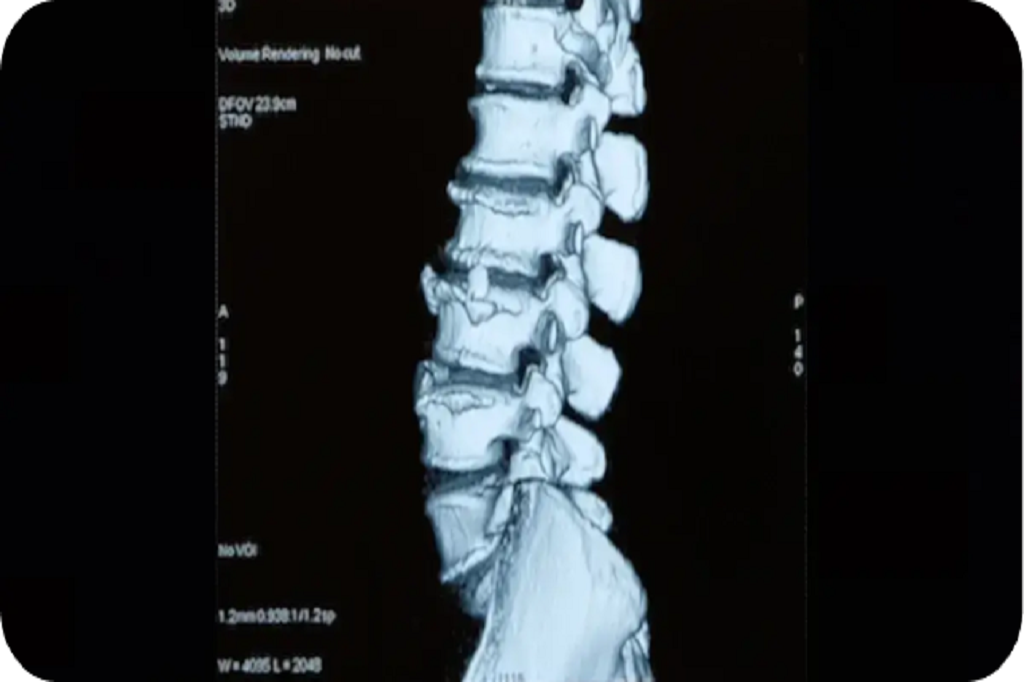

A diagnostic injection to confirm the painful joint and provide relief from spinal arthritis.